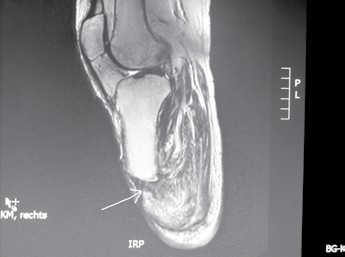

- Bei jeder Amputation handelt es sich um ein plastisches Verfahren mit großer Wund- und Narbenfläche und nicht um das bloße Abschneiden eines Extremitätenteiles. Die in der Spezialambulanz für Amputierte des Verfassers begutachteten Ergebnisse lassen aber vermuten, dass dies noch nicht allen Operateuren klar geworden ist (Abb. 3a–c).

- In vielen Fällen wird schon unmittelbar postoperativ zur Linerversorgung mit oder ohne Pin gegriffen. Dabei sollte der Liner mit Pin wegen seiner negativen Folgen für den Stumpf bis auf ganz wenige Ausnahmen heute für den Unterschenkelstumpf obsolet sein. Aber auch jeder andere Liner ist besonders im Rahmen der Versorgung eines Unterschenkel- oder Syme-Stumpfes in Abhängigkeit von der Grundkrankheit und der damit in Zusammenhang stehenden Konsolidierungszeit bis zur 8. bzw. 12. postoperativen Woche nicht zu empfehlen. Sehr viele Patienten können den Liner nicht von dorsal nach ventral anziehen, sonrdern rollen ihn von ventral nach dorsal auf und reißen dabei die „feinen“ Nähte aus, die die Verbindung zwischen Muskulatur und z. B. Periost darstellen. Die Folge: Das Operationsresultat ist zunichtegemacht, und es entsteht wiederum ein Weichteilüberschuss, den man – z. B. bei einer Revision – gerade beseitigt hatte (Abb. 6a–h).